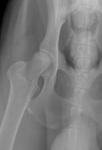

дефект тазовой кости собаки

Симптомы: собака начала хромать и поджимать правую заднюю лапу. Данные симптомы появились около 2х недель назад. Ранее данных симптомов никогда не было. На основании этих симптомов был сделан рентген снимок. Патология на головке бедренной кости.

Диагноз ясен, и, если отбросить тонкости, у Вашего питомца явления выраженного деформирующего коксартроза (артроза тазобедренного сустава). С причиной нужно разбираться. От этого будет зависеть дальнейшая тактика и прогноз. Учитывая молодой возраст собаки, можно предположить не диагностированную в щенячьем возрасте дисплазию тазобедренного сустава.

По снимку мне кажется, что головка правой бедренной кости несколько меньше левой. Но с уверенностью я не могу Вам этого сказать. Я не ветеринар, поэтому правильность формы головки бедренной кости визуально определить не могу. Только МРТ покажет точные размеры костей и полноценность связочного аппарата.